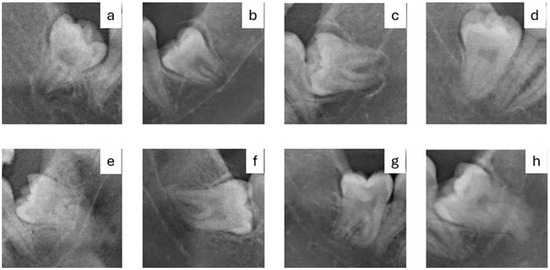

Attempting to Determine the Relationship of Mandibular Third Molars to the Mandibular Canal on Digital Panoramic Radiography; Using CBCT as Gold Standard

by Hilal Isra Erkan, Osman Yalcin, Umut Pamukcu and Kahraman Gungor

(1) Background: It is important to know, radiologically, the relationship of Mandibular third molars (M3) to the mandibular canal to minimize postoperative complications by causing damage to the inferior alveolar vessels and nerve during extraction. This study aimed to evaluate the usability of various image analyses or high-risk radiographic findings in determining the relationship of M3s to the mandibular canal on Digital Panoramic Radiography (DPR). (2) Methods: DPRs of 60 patients with bilateral mandibular M3s in the dental arch, determined one of them to be related to the mandibular canal unilaterally by Cone Beam Computed Tomography (CBCT), were included. The high-risk radiological signs of M3s and Fractal Analysis (FA) and Histogram Analysis (HA) measurements of the trabecular bone around the M3s’ roots were compared. The Independent t-test, Kolmogorov–Smirnov, Mann–Whitney U, and Chi-Square tests were used for statistical analyses. (3) Results: DPR signs, such as radiolucency and bifurcation at the root apex, discontinuity of the mandibular canal cortex, and superimposition of the tooth root and mandibular canal, were observed statistically significantly more frequently for mandibular canal-related M3s (p < 0.05). As an objective image analysis, Lacunarity showed a statistically significant difference between related and unrelated M3s for measurements made inside and outside the mandibular canal (p < 0.05). (4) Conclusions: This study demonstrated that the discontinuity of the mandibular canal cortex and Lacunarity measured on DPR could help determine the relationship of the mandibular M3s to the mandibular canal. Full article